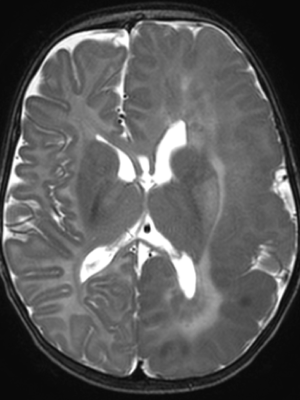

An MRI revealed that Maryam had hemimegalencephaly, a rare neurological condition where one half of the brain is enlarged and can cause epilepsy, developmental delays and muscle weakness. In this case, it had affected the left hemisphere of Maryam’s brain. She was immediately rushed to The Hospital for Sick Children (SickKids).

Epilepsy that doesn’t respond to medication – also known as intractable epilepsy – can be treated with surgery, and the most common surgery to treat conditions like Maryam’s is a functional hemispherectomy. This type of surgery disconnects the part of the brain that is having seizures from the rest of the brain. While the approach has a long-established track record of success in children, it is highly invasive and carries significant risks—particularly for infants as young as Maryam.

Over the course of the next few months, the team did their best to keep Maryam’s seizures at bay while she could get stronger – the hope was that she could undergo surgery in the future. But Maryam would go on to continue to have significant daily seizures – at times spreading to the rest of her body -- an alarming shift that suggested this increase in epileptic activity might now be affecting her previously healthy right hemisphere.

Between February and April 2024, four carefully planned embolization procedures, spaced two to three weeks apart, successfully isolated Maryam’s left hemisphere.

And at every step, the Interventional Neuroradiology team, Epilepsy and Neurosurgery teams worked together, using detailed electroencephalogram (EEG) and brain MRI scans to ensure precision and safety.

Now, months later, Maryam has not had a single seizure since July 2024.

“She went from having seizures about every two minutes to having one or two per day, to then having zero, which is incredible,” says Muthusami.